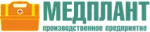

Портативный транспортный пульсоксиметр «Окситест-1» предназначен для неинвазивного непрерывного определения и мониторирования насыщения (сатурации) кислородом гемоглобина периферической артериальной крови (SpO2) и частоты пульса (PR).Преимущества

- Пульсоксиметр оснащен крупными и яркими индикаторами сатурации.

- Обеспечивает индикацию и визуализацию пульсовой волны.

- Разъём датчика – в крепком корпусе, с несимметричной входной частью, исключающей поломку контактов при попытке неверного подключения.

Блок обработки и индикации |

Датчик пульсоксиметрический пальцевой |